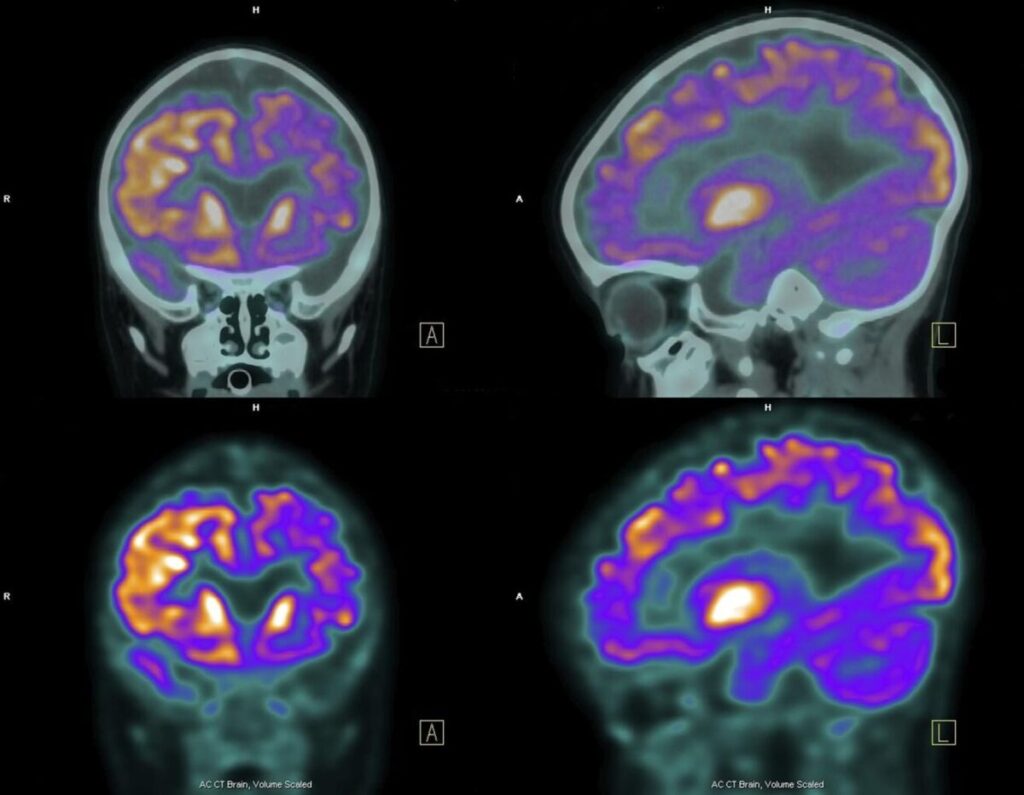

③ PET(陽電子放出断層撮影)1970年代

原理

放射性トレーサーを使い脳代謝を測定。

測定内容

- グルコース代謝

- 神経伝達物質

- 血流

意義

精神疾患研究に革命。

例:うつ病→ 前頭葉代謝低下